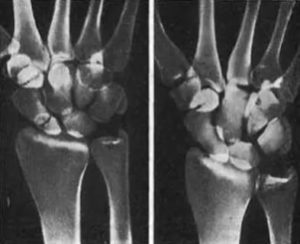

Рис. 27. Рентгенограммы больного 32 лет с несросшимся поперечным переломом ладьевидной кости в проксимальной трети, впервые распознанным через 9 мес. а — через 9 мее после травмы; б — через 1,5 года: усиление рассасывания на концах фрагментов; в, г — через 5,5 мес с начала иммобилизации в контролируемой циркулярной гипсовой повязке при легком сгибании и лучевом отклонении кисти (первая косая и прямая проекции) — консолидация.

лизации путем замены гипсовых повязок через каждые

- 5 нед сращение в сроки от 3 до 4—6 мес наступает в 85—90 % (рис. 27).